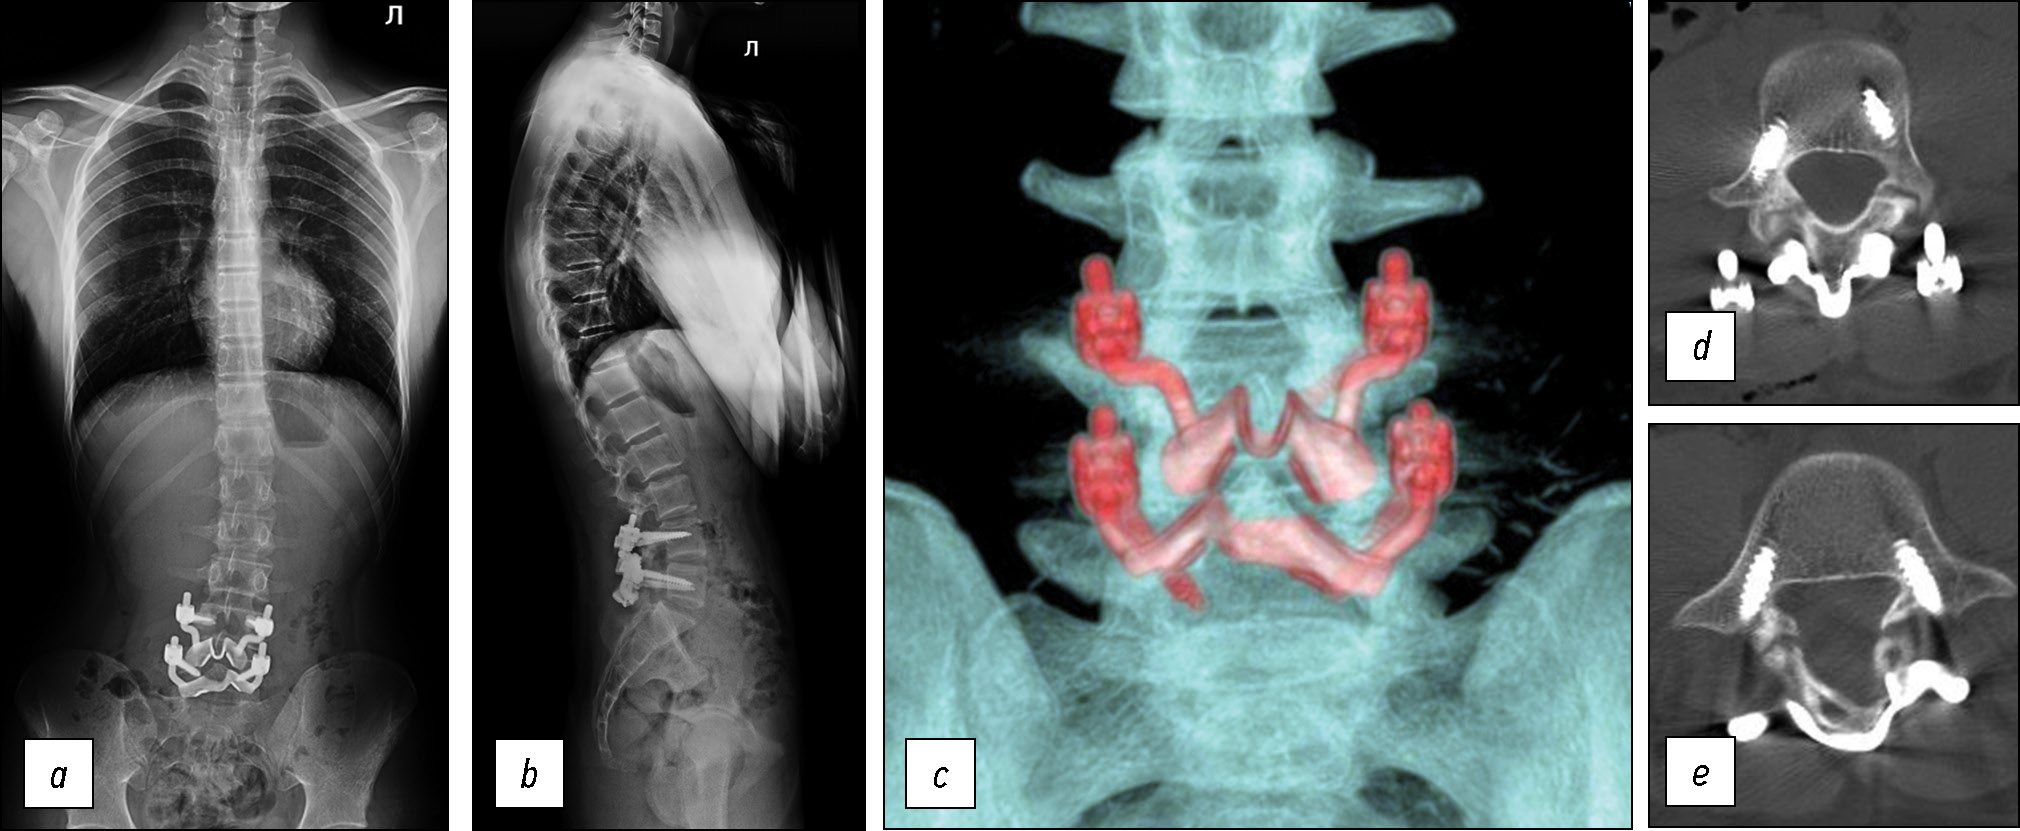

Ход операции: в положении пациента на животе под интубационным наркозом выполнен разрез кожи и подкожно-жировой клетчатки по линии остистых отростков от L4 до S1. Произведено скелетирование дужек L4, L5 позвонков, при этом надостистая связка сохранена. Выполнен гемостаз. Под контролем электронно-оптического преобразователя (ЭОП) произведена установка транспедикулярных винтов через корни дуг в L4 и L5 позвонки с двух сторон с сохранением суставных отростков. С помощью кусачек Керрисона удалена межостистая связка L4-L5, L5-S1. Изогнутым распатором выполнено скелетирование дужек в месте осуществления субламинарной фиксации. Установлена индивидуальная пластина на скелетированную дужку L4 позвонка, причём пластина проведена между остистыми отростками соответственно L4 и L5 позвонков. Аналогичным образом в сформированное отверстие между остистыми отростками L5 и S1 позвонков установлена пластина на скелетированную дужку L5 позвонка. Фиксирующие элементы пластин помещены в головки винтов и фиксированы блокировочными винтами (гайками). Проведён рентген-контроль с использованием ЭОП: положение металлоконструкций корректное (рис. 6). Рана промыта растворами антисептика, послойно ушита. Выполнен внутрикожный косметический шов. Интраоперационная кровопотеря составила 100 мл. Пациент был вертикализирован в первые сутки после операции. Отмечал умеренную боль в области вмешательства, которая регрессировала в течение трёх дней на фоне приёма нестероидных противовоспалительных препаратов. Выполнены контрольное КТ-исследование и постуральная рентгенография позвоночника — подтверждены правильное положение имплантатов и фиксация зоны спондилолиза (рис. 7). На четвёртые сутки после операции пациент выписан из стационара. Рана зажила первичным натяжением.

Рис. 7. a, b — постуральная рентгенография позвоночника, положение конструкции правильное, фиксация зон спондилолиза стабильная, сагиттальный баланс не нарушен, c — КТ поясничного отдела позвоночника, 3D-реконструкция, d — аксиальный срез на уровне L4 позвонка, e — аксиальный срез на уровне L5 позвонка.

Fig. 7. a, b — postural radiography of the spine, the position of the structure is correct, fixation of the spondylolysis zone is stable, sagittal balance is not disturb, c —3D reconstructed CT scan of the lumbar spine, d — axial slice at the level of the L4 vertebra, e — at the level of the L5 vertebra.

Через три месяца с момента операции пациент полностью восстановил объём физических нагрузок. Болевых ощущений в поясничном отделе позвоночника не отмечает (Ped`s QL — 96 баллов, VAS — 0 баллов). По данным функциональной рентгенографии поясничного отдела позвоночника — положение имплантатов корректное, фиксация стабильная, движения в позвоночно-двигательных сегментах, на которых проводилось оперативное вмешательство, сохранены (рис. 8).